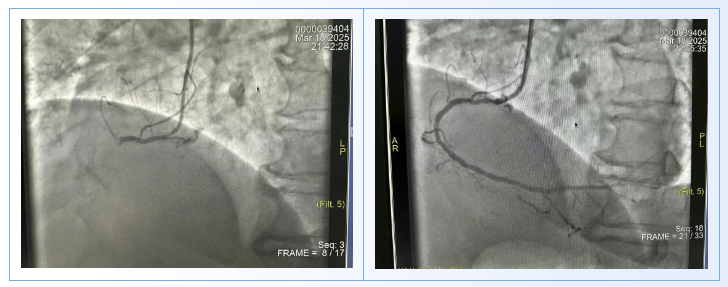

急诊重症医学部急救医护小组携带胸痛转运急救箱护送患者绕行CCU,直达心脏介入中心。心内一科副主任杨俊杰带领心脏介入团队再次确诊患者为急性下壁心肌梗死,冠脉血管病变严重,必须立即开通血管。术中冠脉造影显示多支病变,右冠动脉近段闭塞,狭窄100%,前降支狭窄90%,回旋支中段95%狭窄,心脏介入团队对右冠闭塞支实施血栓抽吸、球囊扩张并植入支架一枚,术中患者心跳极度过缓,应用抢救药物后心率逐渐恢复正常,成功开通血管,患者生命体征恢复平稳。从患者进入总院区到手术结束,仅用时40分钟,远低于国际标准的90分钟,创造了“高铁”般的救治速度。